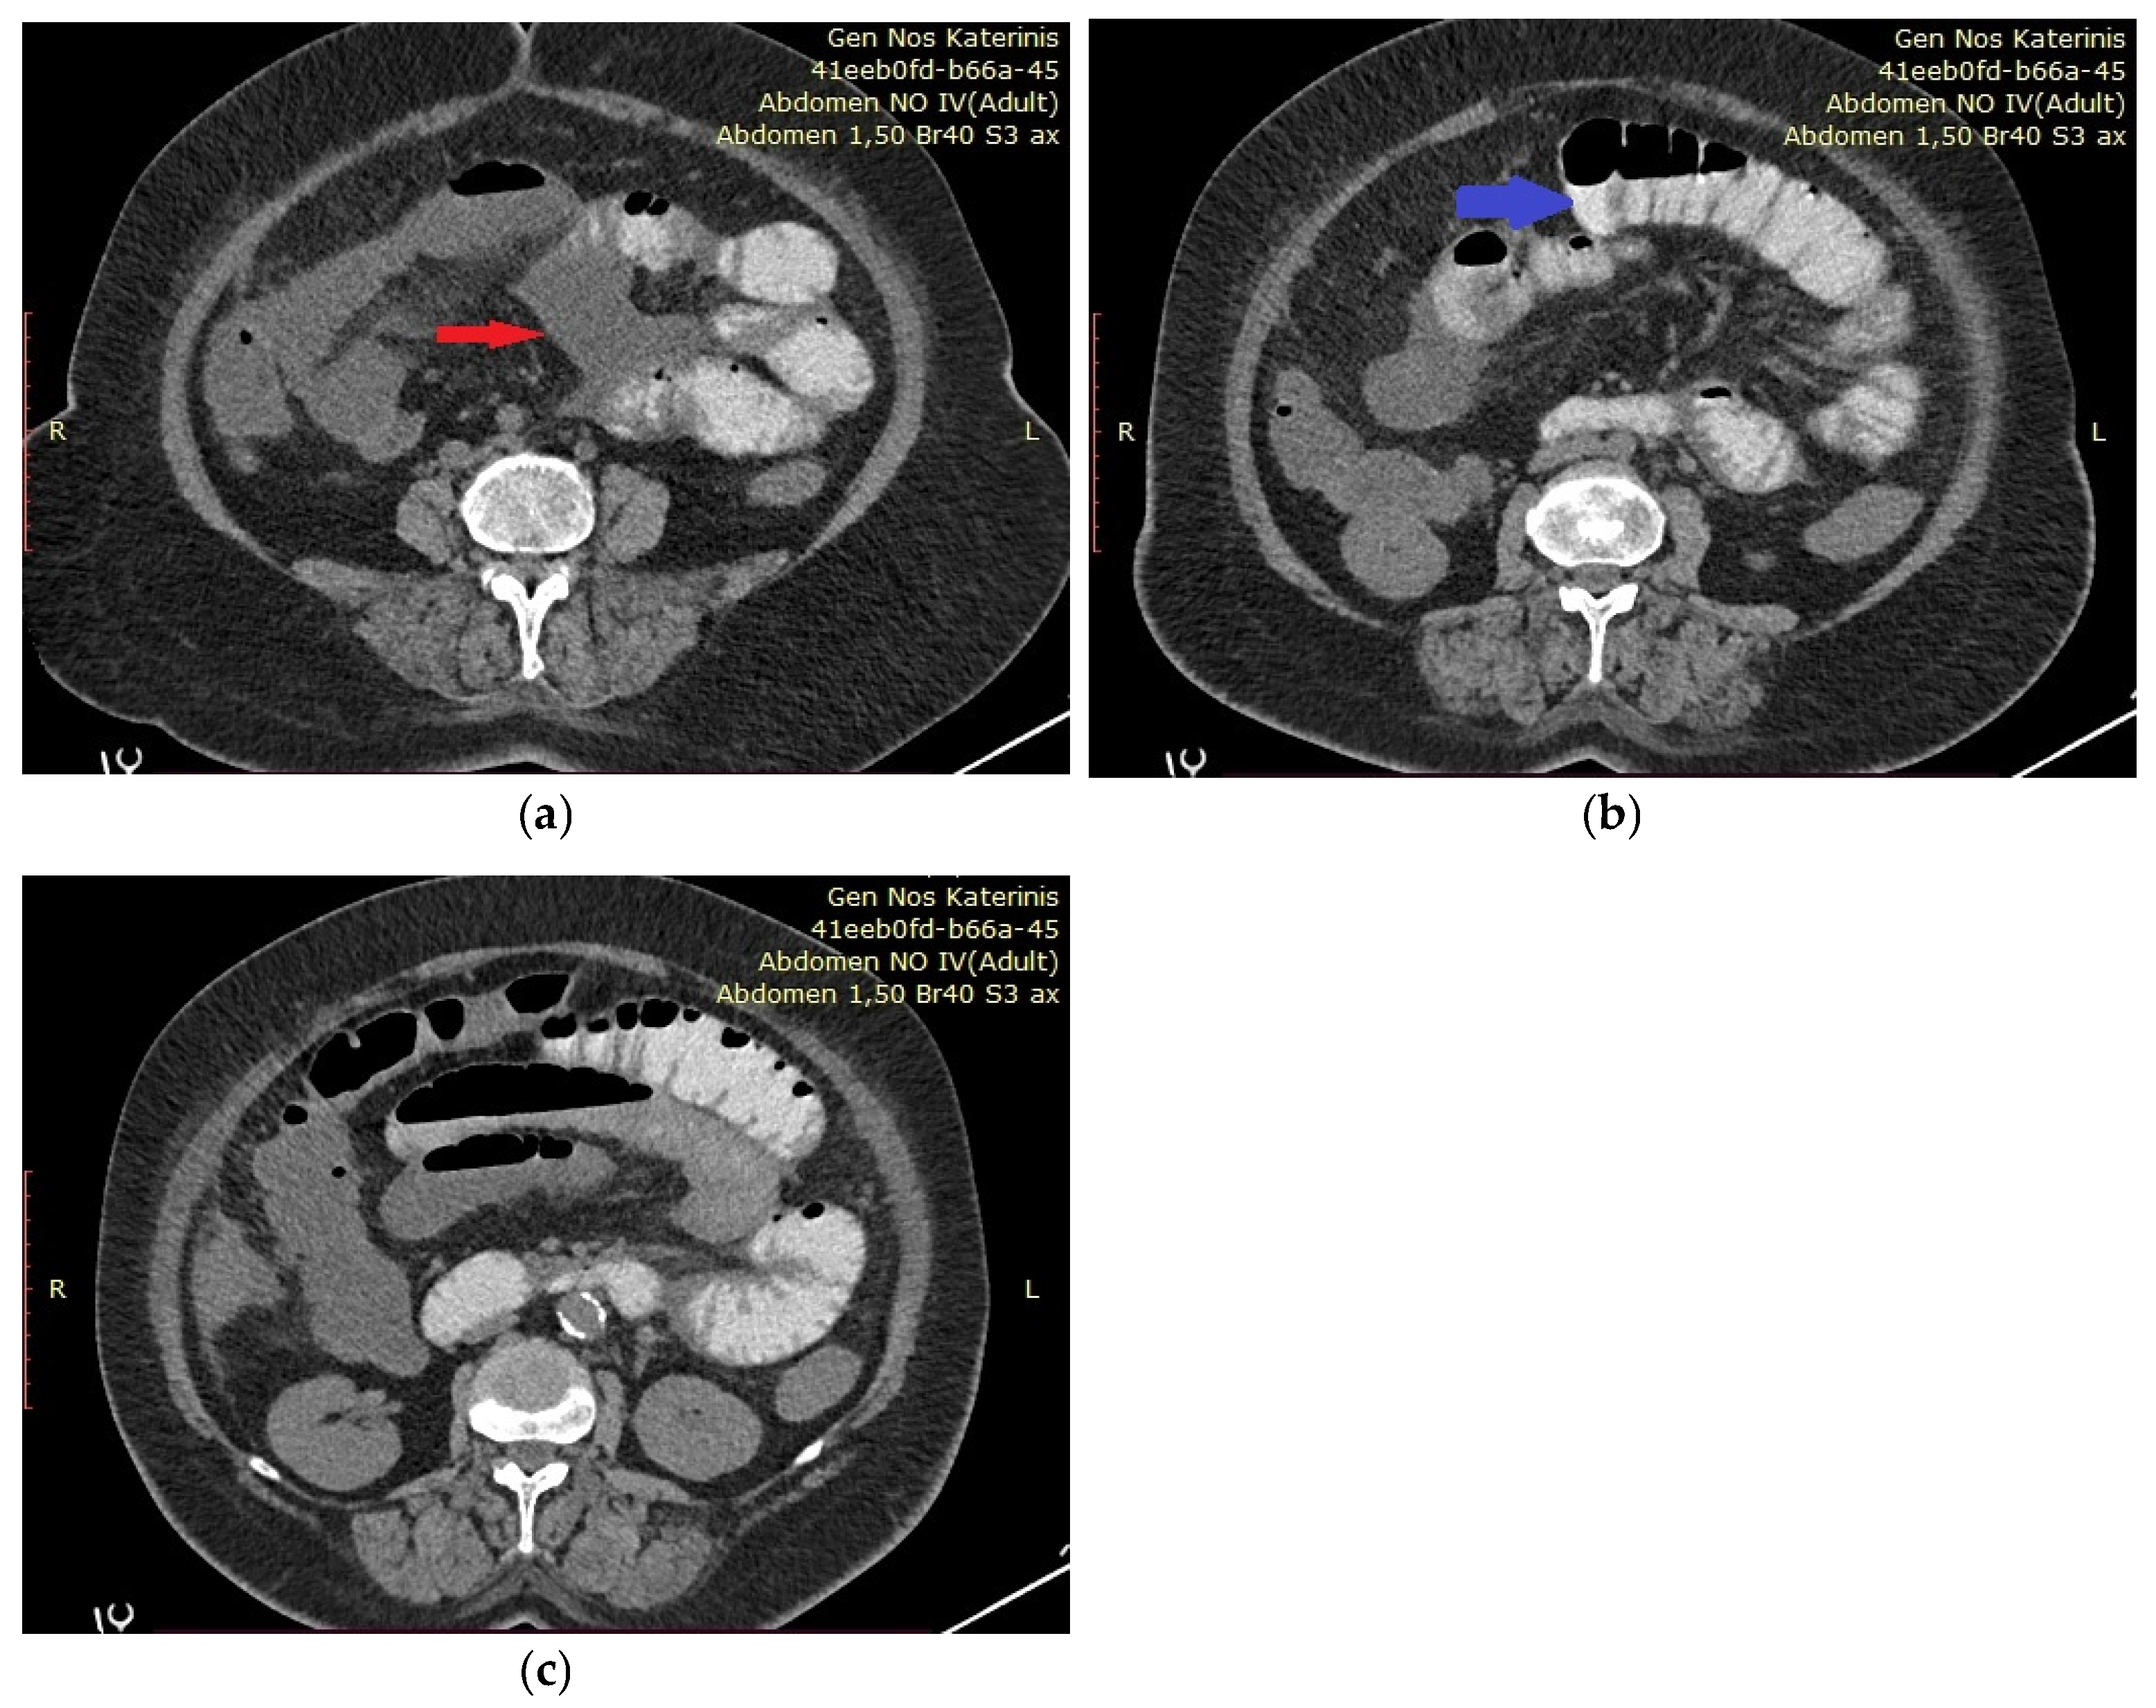

Figure 1. (ac) We present the case of a 62-year-old woman who presented to the Emergency Department of the General Hospital of Katerini, Greece, complaining of acute abdominal pain, fever, and general discomfort. She reported that she was suffering from non-Hodgkin lymphoma and was obese. She received no medication and reported no other medical conditions. The patient was initially hemodynamically stable, and physical examination revealed generalized abdominal tenderness upon palpation. Laboratory tests showed an elevated white blood cell (WBC) count of 14.74 × 103/μL and a C-reactive protein (CRP) level of 32 mg/dL, while her hematocrit (HCT) was 28.6% and her hemoglobin was 10.6 g/dL. Due to the patient’s reported allergies, an abdominal computed tomography (CT) scan without intravenous contrast was performed, revealing dilated small bowel loops and free intraperitoneal fluid, without evidence of bowel obstruction or signs of malignancy. (a) The red arrow indicates free intraperitoneal fluid. (b) Dilated small bowel loops are indicated by the blue arrow. (c) The air–fluid levels are indicative of ileus.